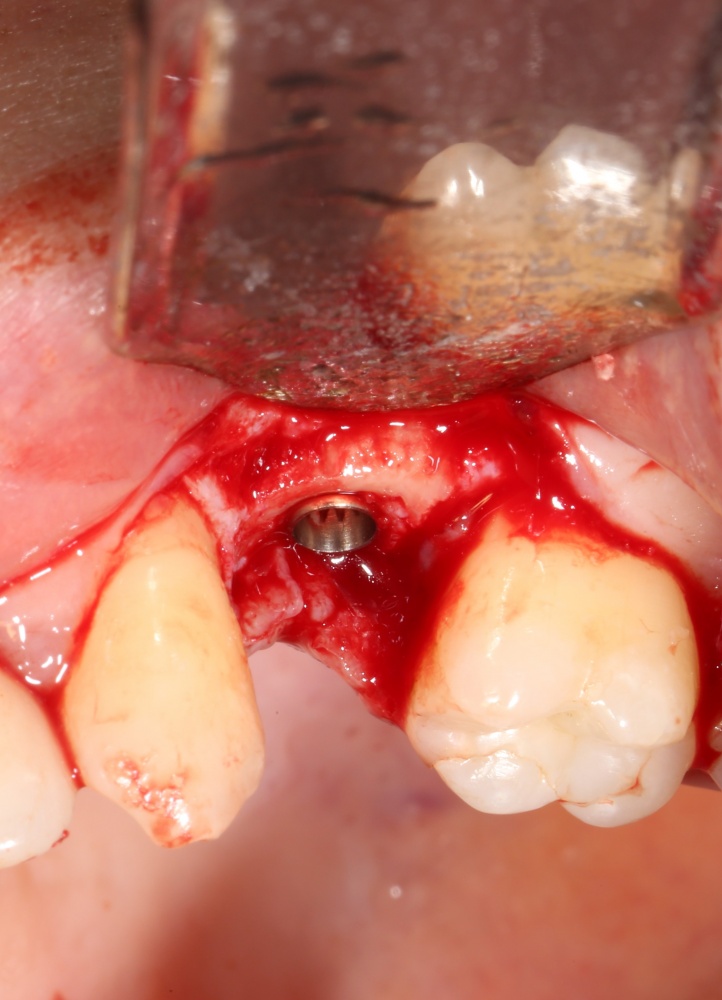

Кроме всего вышесказанного можно добавить, что само положение дефекта упрощает АТККФ и снижает её травматичность, что при I-II биотипе по Миру НКР не так эффективна, как хотелось бы, и т. д. Но тут можно много спорить, лучше один раз показать:

Забор костного фрагмента проводится с наружной косой линии с помощью ультразвукового пьезохирургического инструмента. Ничего сверхнового и супернеобычного тут нет, совершенно стандартная методика. С той лишь разницей, что молоток для этого используют только фашисты и только в гестапо использовать не нужно, всё делается усилием и ловкостью рук.

Нюансы начинаются с обработки принимающего ложа. Да-да, уважаемые друзья, одна из причин некроза блоков, их чрезмерной атрофии и прочих проблем — в отсутствии обработки принимающего ложа. Некоторые делают дырки, но правильнее и эффективнее поступить так:

то есть, просто снять слой кортикальной пластинки с участка, к которому будет фиксироваться костный блок. Почему? Читайте здесь>>.

Вторая особенность — мы не адаптируем и не обрабатываем костный блок invitro, а фиксируем его так, как есть:

после чего обрабатываем — доводим до окончательной формы альвеолярного гребня:

Далее, можем приступить к установке имплантатов. Разумеется. по хирургическому шаблону:

Последняя картинка даёт представление о том, какой объем костной ткани мы «нарастили».